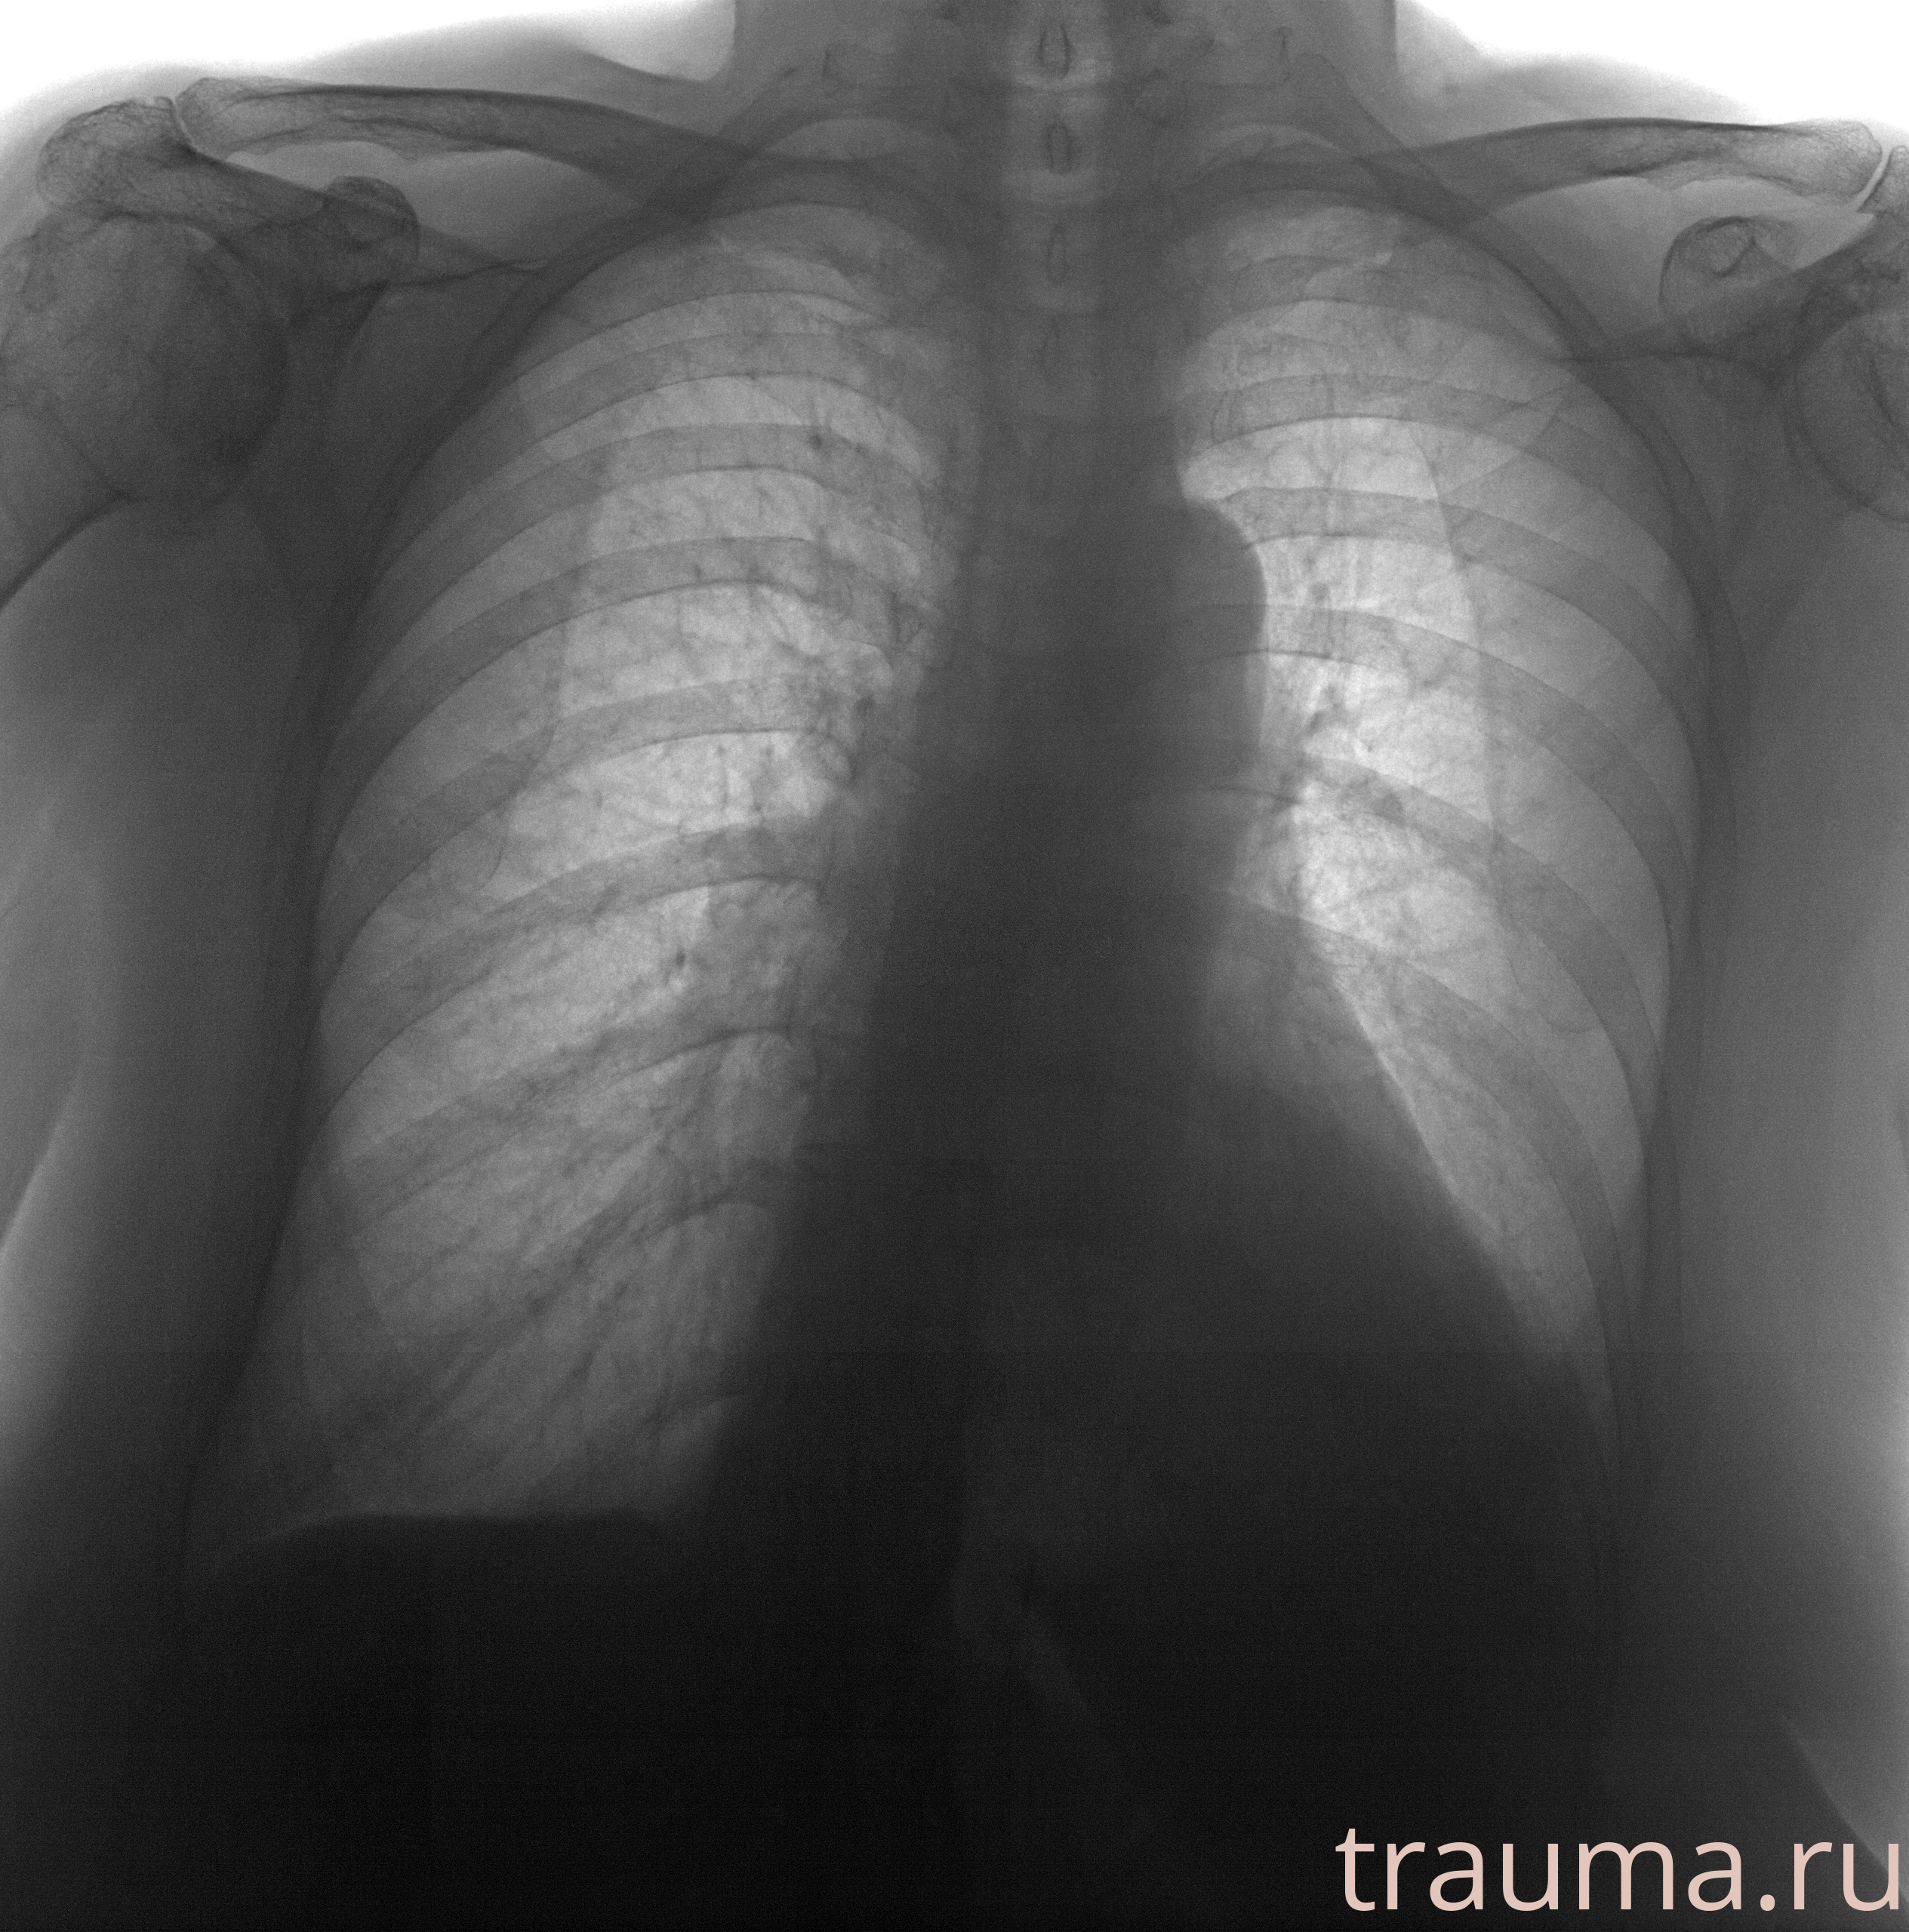

Рентген на дому: по вашему адресу приезжает врач-рентгенолог, травматолог-ортопед с мобильным рентгеновским аппаратом, проводит диагностику травмы или заболевания, делает необходимые рентгенограммы, дает рекомендации по дальнейшему лечению. Получить качественные снимки в домашних условиях возможно благодаря уникальной методике, разработанной МосРентген Центром для института  Склифосовского

при переломе шейки бедра и пневмонии от компании МосРентген Центр - партнера Института имени Склифосовского